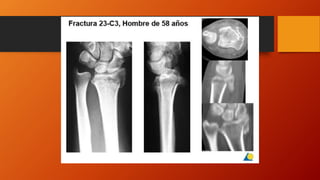

Clasificación AO

• Es importante recalcar la importancia que

ha tenido la AO en el tratamiento y manejo

de las fracturas desde hace muchos años

hasta la fecha y en la muñeca no es la

excepción. Los tres tipos básicos se

subdividen en grupos y subgrupos hasta

completar 27 subtipos posibles de

fracturas.

• La zona anatómica que corresponde al

cúbito y radio es la zona 2 y la epífisis

distal corresponde al número 3 (siendo 1 la

proximal y 2 la diafisaria) Así pues todas

las fracturas radiocubitales distales

comenzara por los números 23, es decir,

zona anatómica 2 (radio y cúbito) y 3

refiriéndonos a la parte distal.